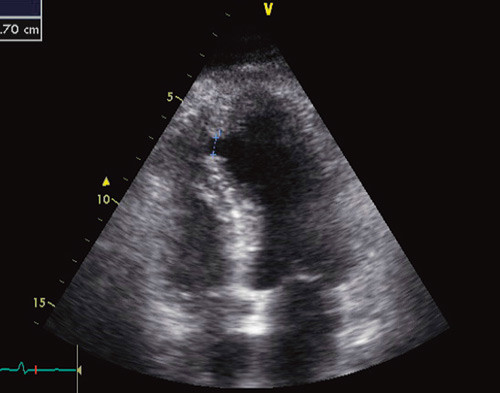

Ekkokardiografi kort tid etter innleggelsen ga mistanke om ventrikkelseptumruptur, og pasienten ble umiddelbart transportert til St. Olavs Hospital.

Ekkokardiografi er nødvendig for å skille mellom ventrikkelseptumruptur og akutt mitralinsuffisiens. Ved hjelp av ekkokardiografi lokaliseres rupturen. Shuntfraksjonen kan beregnes for å vurdere størrelsen av rupturen. I tillegg får man informasjon om infarktstørrelse, mitralinsuffisiens og ventrikkelfunksjon.

Utredning ved St. Olavs Hospital med ny ekkokardiografisk undersøkelse viste infarktskade over apikale septum, for øvrig hyperdynamisk ventrikkel med ejeksjonsfraksjon på 50 %. Det ble påvist en ruptur i apikale septum med diameter 7 mm og 2 : 1 shunt (fig 2). Koronar angiografi viste 90 % stenose i midtre avsnitt av fremre nedadstigende gren av venstre koronararterie (LAD), for øvrig ingen signifikant koronarpatologi. Pasienten var fortsatt hemodynamisk stabil med normalt blodtrykk, men økt hjertefrekvens på 90 slag/min. Biomarkører for hjertemuskelskade ved ankomst viste CK-MB-masse 172 µg/l (normalt < 5 µg/l) og troponin T-verdi 4,330 µg/l (normalt < 0,01 µg/l). Øvrige laboratorieverdier var uten anmerkning.